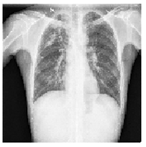

Dataset and Implementation Details:

For the supervised segmentation, we used our PPAU-Net model and KLTV as the loss function. We compared against all the preliminary segmentation models and TV loss. Then we performed semi-supervised multi-tasking for semi-supervised disease classification and lung segmentation from chest X-ray images. We used three chest X-ray datasets: the Montgomery County chest X-ray set (MCX) comprising 138 images, the Shenzhen chest X-ray set (SCX) comprising 527 images [17], and the JSRT dataset (JCX) comprising 247 images [18]. In addition, we created another dataset (CCX) comprising 912 images, by combining prior datasets. Each dataset was split into train and test sets in a 75:25 ratio and 10% of the train set was used for model selection. Except for CCX, all the datasets were used for binary classification (normal/abnormal), while CCX was used for 3-class classification (normal, nodule, tuberculosis). The X-ray images were normalized and resized to pixels. For multi-tasking, we used the Adam optimizer with momentum 0.9 and learning rates and . Each model was trained using a mini-batch size of 16. All the convolutional layers were followed by batch-normalization, except for the convolutions that generate side-outputs. We performed dropout at a rate of 0.4 in the discriminator. Each model was evaluated after training for 300 epochs. For the classification, along with the overall accuracy, we reported the class-wise F1 scores. For the segmentation, we used the following performance metrics: Dice similarity (DS), Average Hausdorff distance (HD), Jaccard index (JI), Sensitivity (SN), Specificity (SP), F1 score, Structural Similarity Measure (SSIM), Precision (PR), and Recall (RE) scores.

For performance evaluation of the proposed model and a list of other models as baselines, we made use of the following three publicly available datasets: the Montgomery County chest X-ray set (MCX), the Shenzhen chest X-ray set (SCX) available from NIH [17], and the JSRT dataset available from Japanese Society of Radiological Technology [18] (JCX). An additional dataset was created combining all of them (CCX). Table 3 shows the partitioning of the datasets for the four different settings. We used or prepared the images as follows:

MCX: In this dataset, there are 138 frontal X-Rays: 80 X-Rays are normal and 58 X-Rays show manifestations of Tuberculosis. This dataset contains separate left and right lung ground truth masks, which we combined in our experiments.

SCX: This dataset comprises 662 frontal chest X-rays. Of them, 336 are normal X-Rays and 326 are abnormal cases with manifestations of TB, including pediatric X-rays. After carefully examining all the cases, we selected 527 X-rays in good agreement with the corresponding ground truth lung masks: 248 normal and 279 x-rays with abnormalities.

JSRT: This dataset contains 247 chest X-rays in which 154 images show pulmonary lung nodules and 93 images show no lung nodules. In addition to the lung masks (separated left-right), this dataset includes ground truth masks for the heart and clavicles (separated left-right).